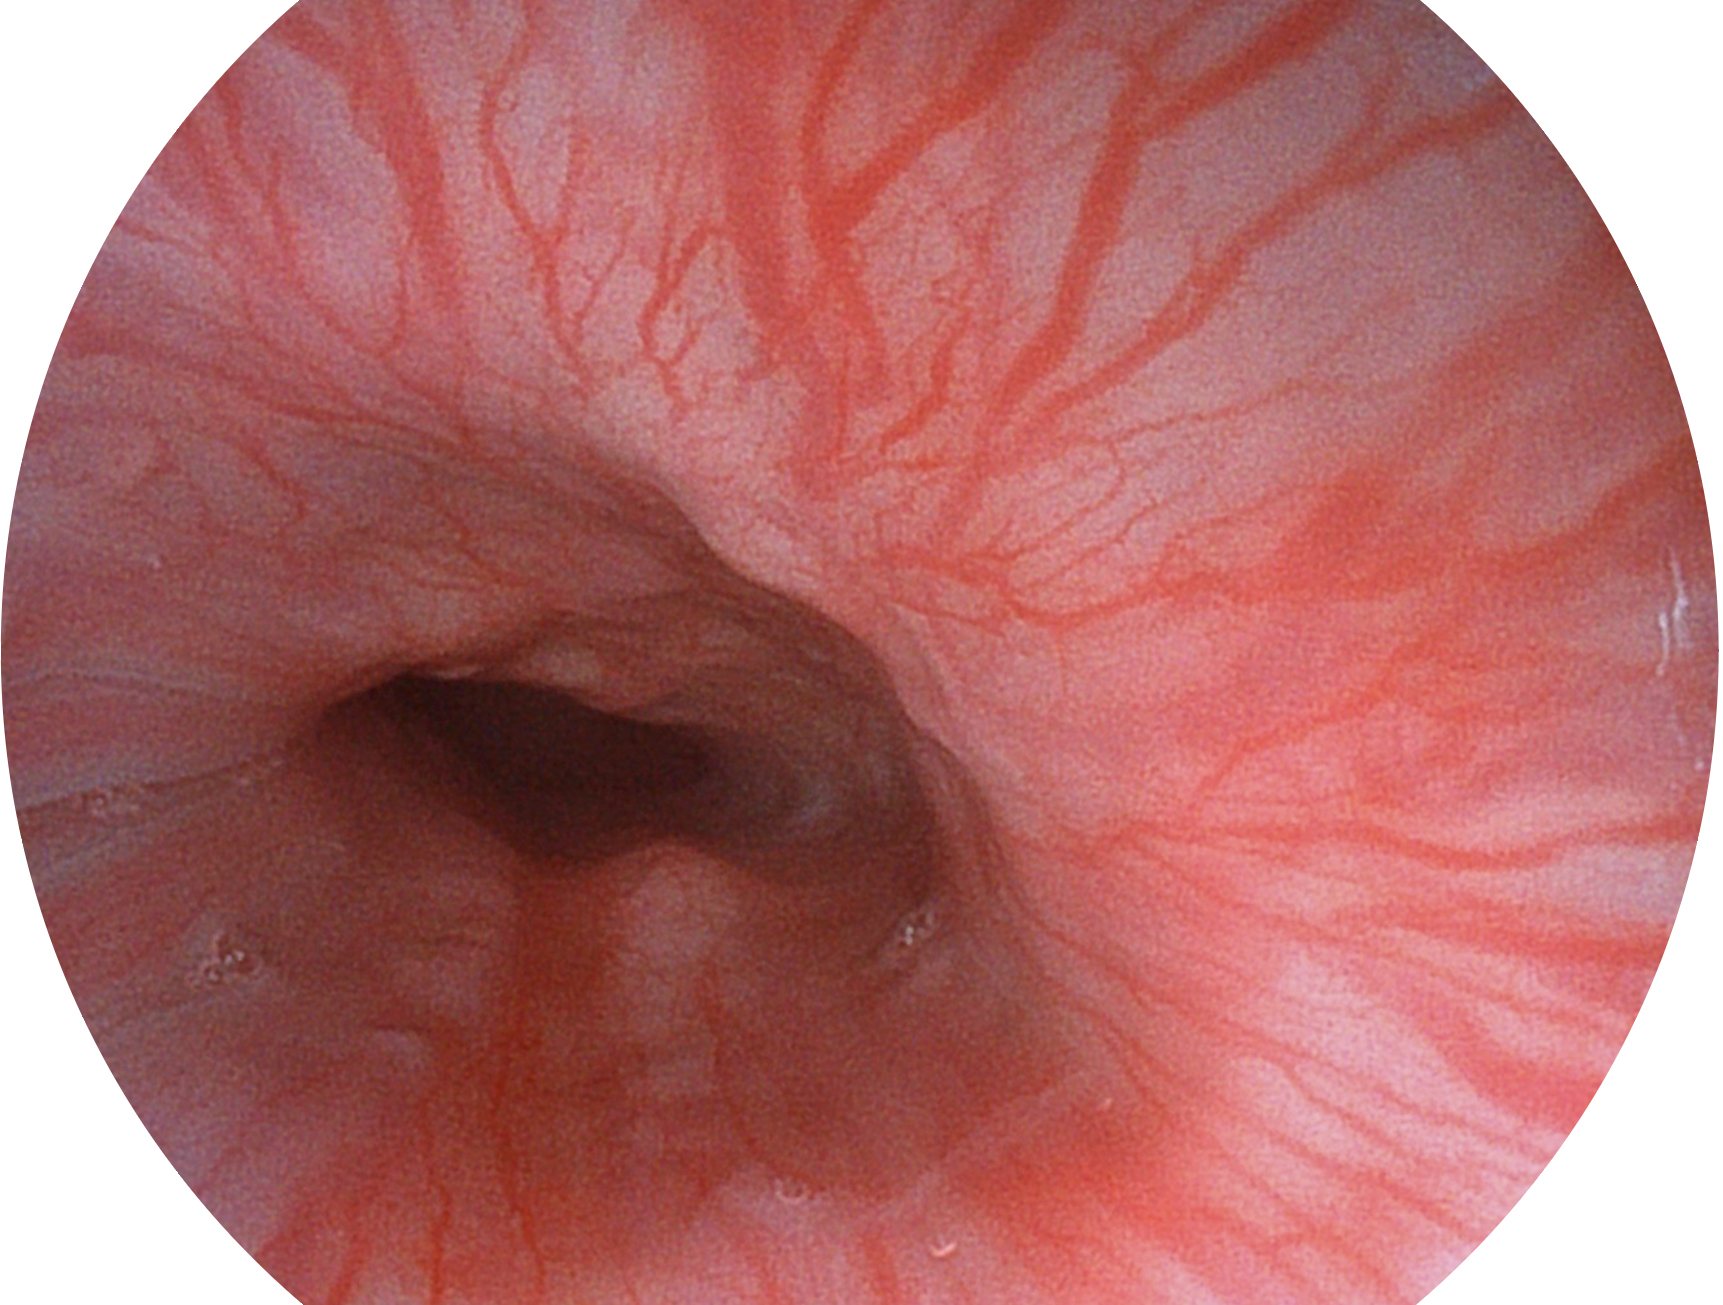

16877太阳集团新开发的内镜染色技术,主要是基于多波长LED 光源的开发,VLS-55Q 四波长LED 光源是由四个不同颜色的LED光按照相应照明模式所规定的特定发光比例进行合束后形成,合束后形成的照明光的光谱由红光、绿光、蓝光及蓝紫光这四个不同的波段范围构成。具有更高光谱自由度,通过光谱比例的控制,实现了聚谱成像技术,英文全称为“Spectral Focused Imaging, SFI”,缩写为“SFI”和光电复合染色成像技术,英文全称为“Versatile Intelligent Staining Technology, VIST”,缩写为“VIST”。